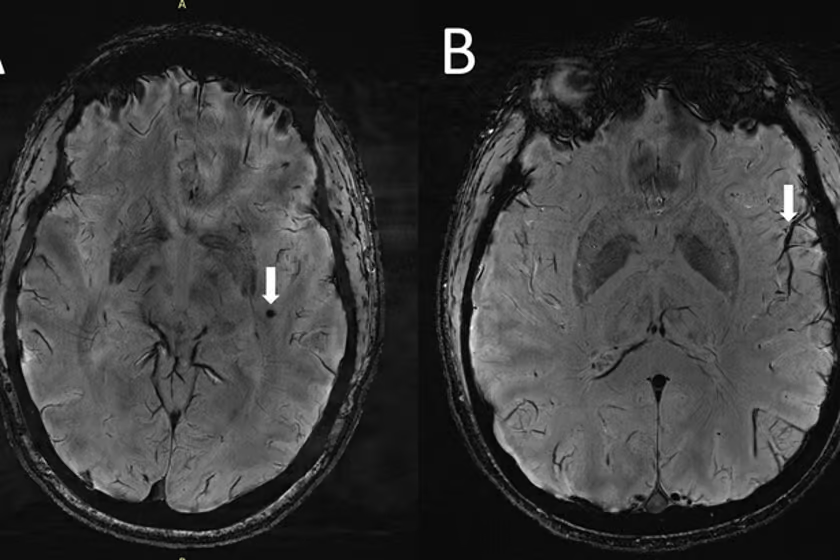

از جملهی این تغییرات، خونریزیهای کوچک مغزی، همراه با بزرگ شدن فضاهای اطراف عروق در ناحیه مرکزی سِمیاُوال(centrum semiovale) در مغز مبتلایان به میگرن بود.

ژو میگوید: در افراد مبتلا به میگرن مزمن و میگرن اپیزودیک بدون هاله، تغییرات قابل توجهی در فضاهای اطراف عروق ناحیهای از مغز به نام centrum semiovale وجود دارد. این در حالی است که این تغییرات تاکنون هرگز گزارش نشده بود.